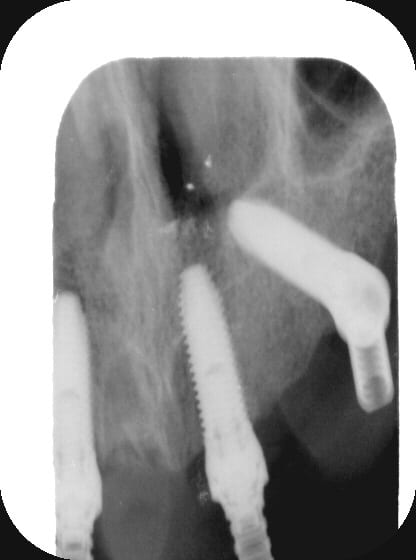

Ci-joint qq images de mon dernier petit All-on-"FOUR" qui date de la semaine dernière.

P1000812 gqllw9 - Eugenol

P1000663 t3yc0w - Eugenol

P1000816 mchm9u - Eugenol

009 fx01gm - Eugenol

024 vownvo - Eugenol